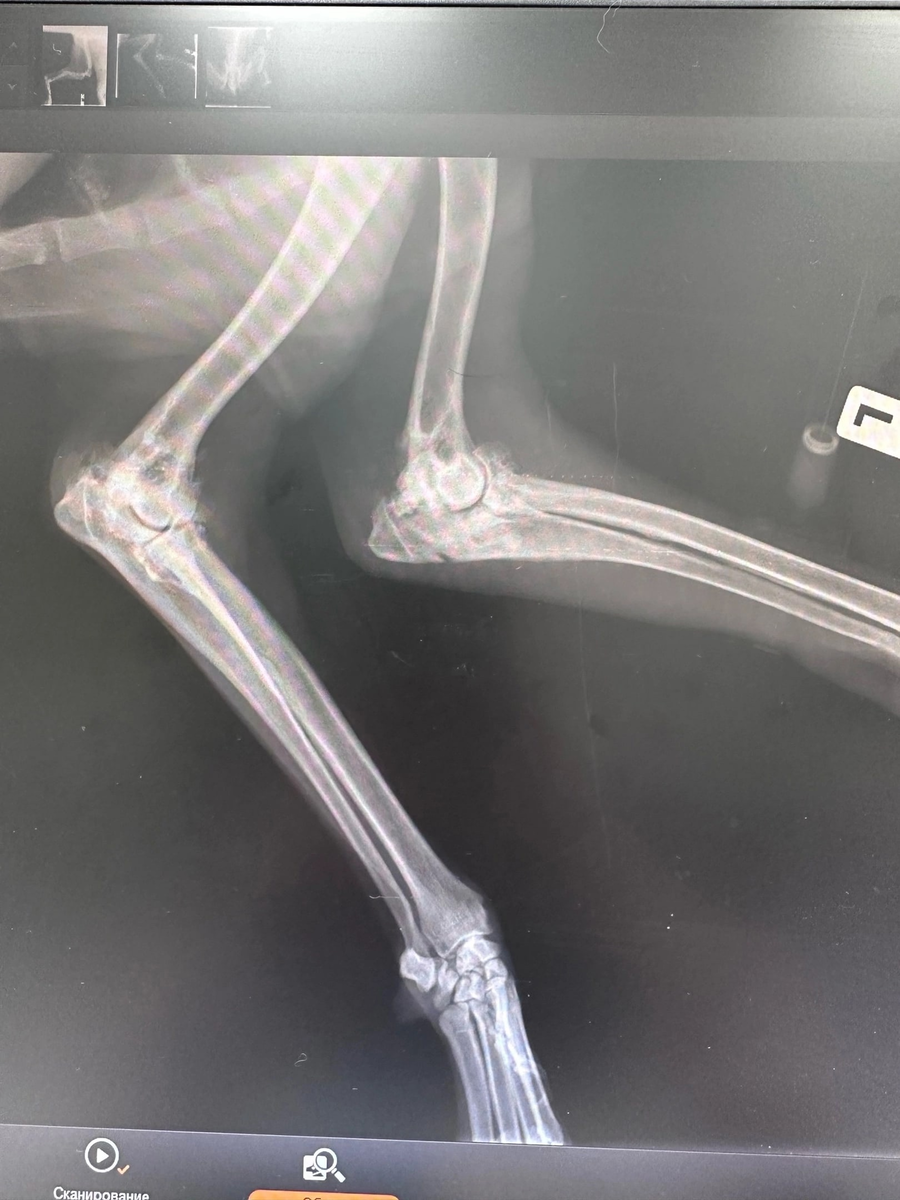

Операция прошла успешно, сломанная конечность была сломана и Снежок (так назвали этого дедушку) хорошо вышел из наркоза! Сейчас Снежок на домашней передержке, схомячил порцию мяса и через короткое время вовсе расслабился, начал облизывать руки человека. Что может быть сильнее мысли, что мы с вами смогли помочь собаке, которая уже не ждала ничего хорошего? Это волшебно! Спасибо каждому за помощь, за быстрое реагирование и, конечно, внимание 💙

Операция прошла успешно, сломанная конечность была сломана и Снежок (так назвали этого дедушку) хорошо вышел из наркоза!